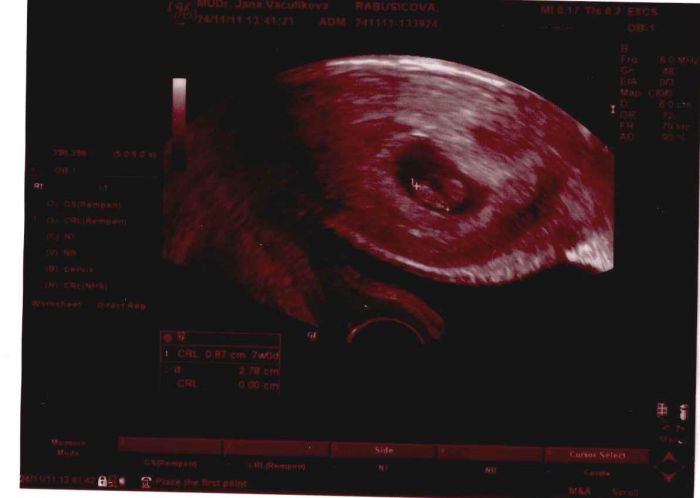

[60634] Evi to víš že jo jo:) čím dál víc se bude podobat človíčku krásnému teda moje mimšo už se podobalo já mněla v 6+2tt skoro taky takovou fotečku ale spíš jako šlo určitě více vidět taková hrudečka,ale ono kolikrát hrozně záleží na tom jaký má dr.UTZ viděla jsem fotky aji od známe na pc a jako nevím kde byla u dr.ale bylo to fakt hrozný všechno rozmazaný a všechno šedýý bléé ale ty máš krásnou a jde tam vidět ten flíček neboj :)

[60672] Ale je to mazec, stačí pár týdnů a je to takový rozdíl :-))